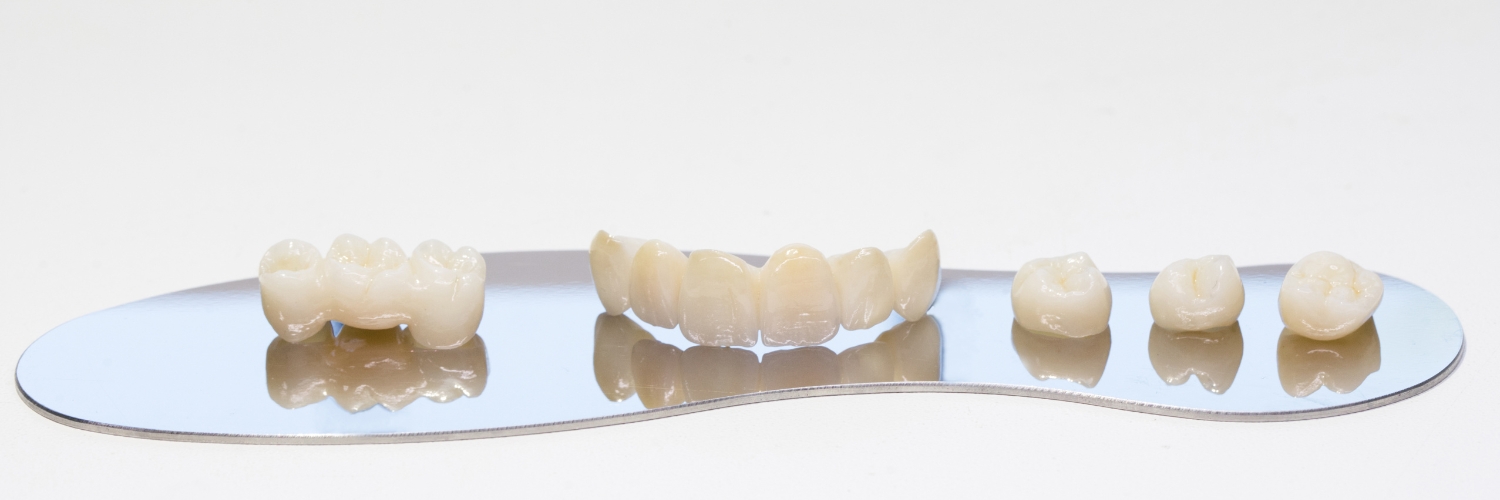

HOIDOT PURENTAVAIVOIHIN

On paljon hammasvaivoja, joihin on olemassa helppojakin hoitoja. Asiantuntevalta hammaslääkäriltä saat hammastarkastuksessa analyysin oman suusi terveydestä. Tässä kuvassa potilaan vaivana oli purressa lohkeavat hampaat. Kyseessä oli kuluneiden hampaiden väärään asentoon ohjaama (eli ristipurentaan) purenta ja sen myötä syntyneet lisävauriot, kulumat ja lohkeamat. Nämäkin hampaat hoidettiin kuntoon, suun terveys palautui ja ilmeestä tuli entistä ehompi, raikas ja hurmaava. Lue koko purentahoidon eteneminen tästä ja katso hämmästyttävät kuvat ennen ja jälkeen.

Purennan tasapainottaminen, jumppailu, purentakisko ja purennan korotus ovat konsteja, joilla saadaan merkittävää apua hampaiden purennallisiin ja esteettisiin haasteisiin.